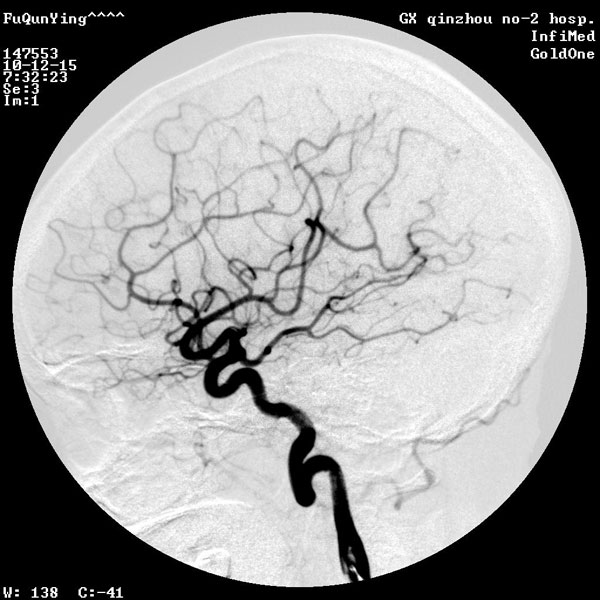

脑血管数字减影造影技术

脑血管数字减影造影 (DSA)是检查脑血管病的最有效方法,不但能清楚地显示颈内动脉、椎基底动脉、颅内大血管及大脑半球的血管图像,还可测定动脉的血流量,所以,目前已被应用于脑血管病检查,特别是对于动脉瘤、动静脉畸形等定性定位诊断。其不但能提供病变的确切部位,而且对病变的范围及严重程度亦可清楚地了解,为手术提供较可靠的客观依据。另外,对于缺血性脑血管病,也有较高的诊断价值。DSA可清楚地显示动脉管腔狭窄、闭塞、侧支循环建立情况等,对于脑出血、蛛网膜下腔出血,可进一步查明导致出血的病因,如动脉瘤、动静脉畸形、动静脉瘘等。

脑血管造影术是检查脑血管病的最有效方法之一。它是通过将含碘造影剂注入到颈内动脉或椎动脉,使脑血管显影,来了解脑血管本身的形态和病变,以及病变的性质和范围。这项检查对诊断脑血管病具有特殊价值。